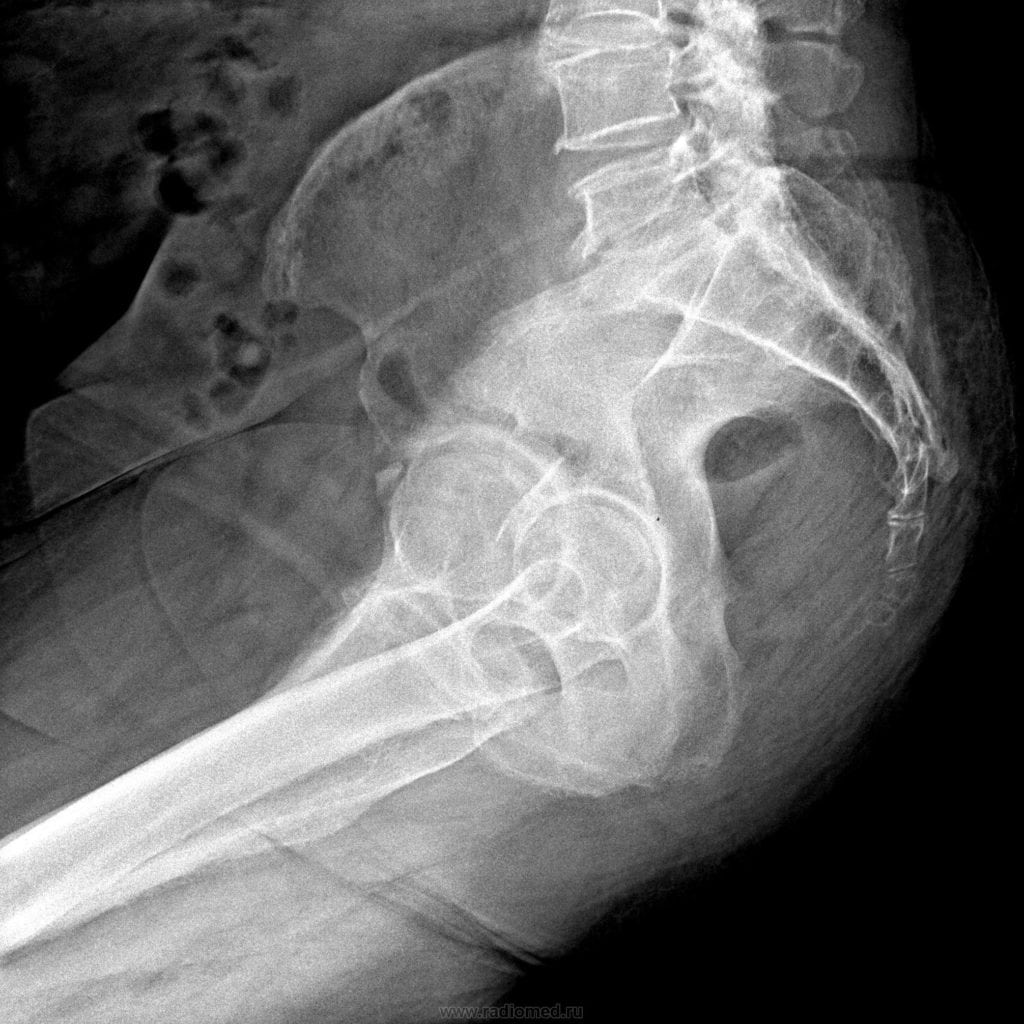

Рентген

Исследование помогает выявить причины, приведшие к болезненности копчика. С помощью рентгенографии можно диагностировать поясничный остеохондроз, межпозвоночную грыжу, спондилолистез. Процедура позволяет установить также стадию заболевания, степень поражения тканей, количество возникших осложнений.

Рентген копчика.